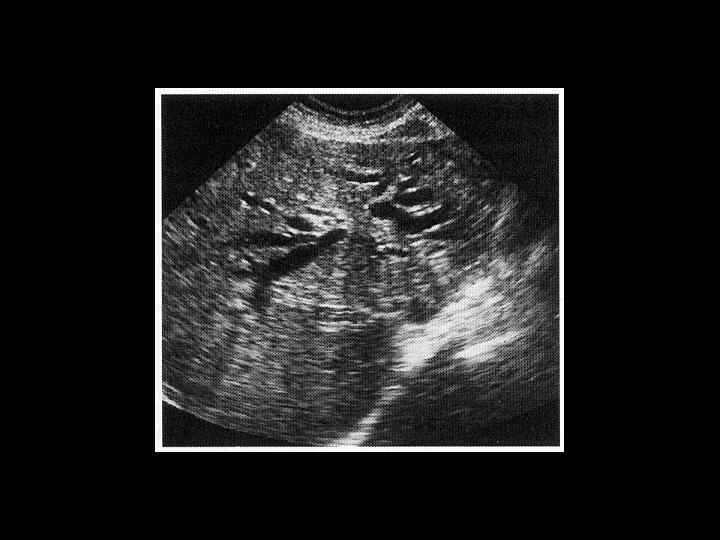

АКТУАЛЬНЫЕ ВОПРОСЫ РЕНТГЕНОЛОГИИ ЛУЧЕВАЯ ДИАГНОСТИКА ЗАБОЛЕВАНИЙ ЖЕЛЧЕВЫДЕЛИТЕЛЬНОЙ СИСТЕМЫ Острый и хронический холецистит УЗ семиотика